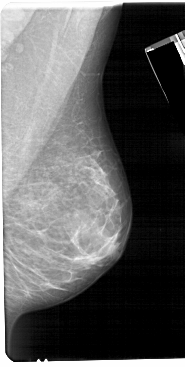

A_1673_1.LEFT_MLO

LEFT_MLO LINES 5491 PIXELS_PER_LINE 2806 BITS_PER_PIXEL 12 RESOLUTION 43.5 OVERLAY